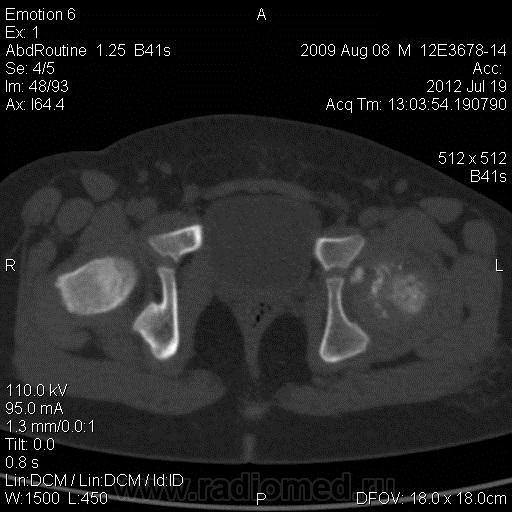

До этого момента никаких претензий и жалоб не было. При поступлении проводилось рентгенологическое исследование тазобедренных суставов в прямой проекции, которое выявило их патологию и стало причиной госпитализации. В стационаре были проведены общеклинические методы исследования (ОАК, ОАМ, б/х крови, серологическое исследование крови) - без изменений. Отмечается выраженное ограничение ротационных движений в левом тазобедренном суставе и незначительное ограничение сгибания (не буду утруждать Вас углами). Учитывая неясные изменения в тазобедренных суставах было решено и проведено КТ исследование их. Это исследование не только не помогло, но и задало еще больше вопросов. Смущают выраженные изменения в эпифизе левого тазобедренного сустава, да и правый тоже неидеален. Для болезни Пертеса слишком малый возраст и выраженные изменения для этого возраста, а также смущает наличие нескольких (3-х) свободно лежащих тел костно-хрящевой плотности, расположенных на достаточно большом расстоянии от самого эпифиза.

Наверное, стадия фрагментации.